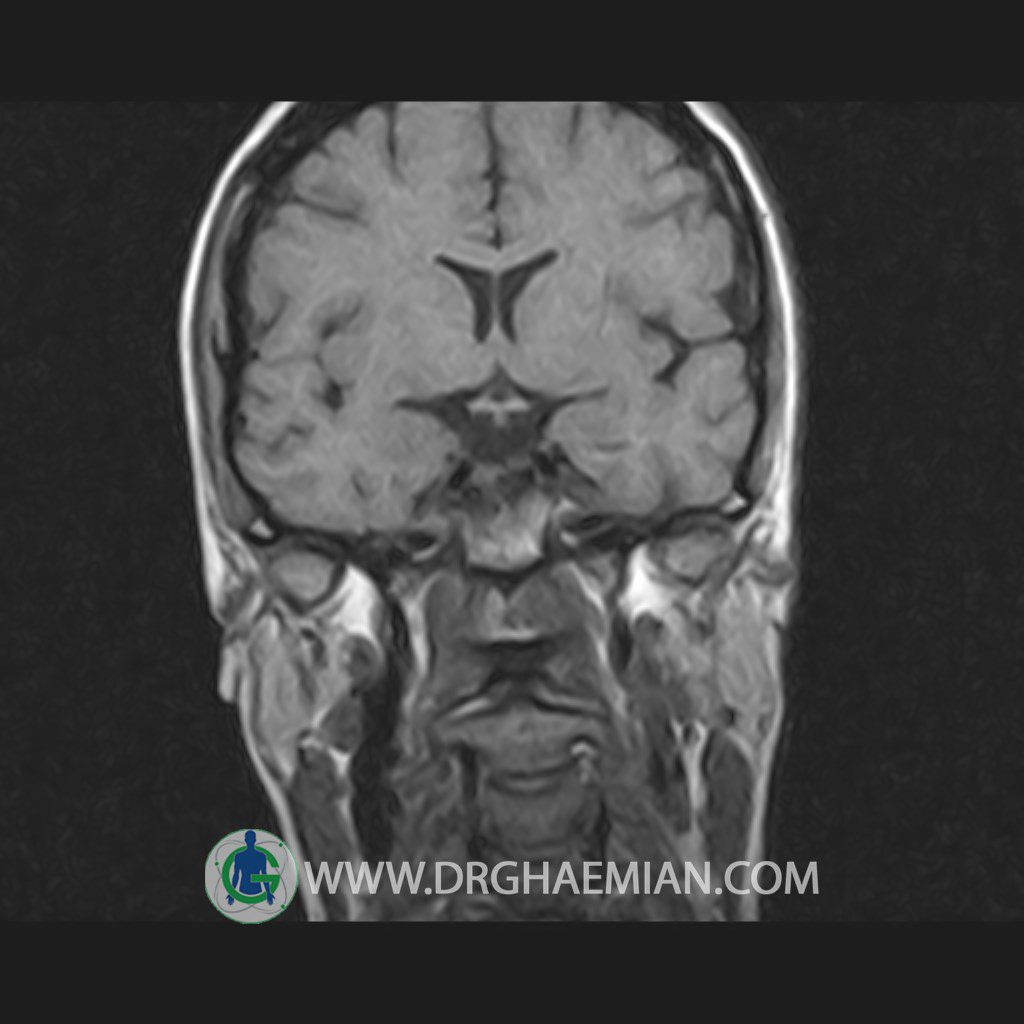

پزشکان اغلب از تصویربرداری ام آر آی برای تشخیص و درمان عارضه های پزشکی که فقط با استفاده از اشعه ایکس یا میدان مغناطیسی و امواج رادیویی قابل مشاهده است، استفاده می کنند. دستگاه ام آر آی تصاویر دقیق از ساختار های داخلی بدن ایجاد می کند. در این کیس هیپرپلازی هیپوفیز و آدنوم مشاهده می شود.

HYPOPHYSIS MRI

(with and without contrast)

Technique: Axial , coronal T1 , Axial , coronal , sagittal T2 , Axial, coronal T1 post Gd & 64 dynamic thin coronal slices.

REPORT :

The sella shows normal size , position and configuration .

The borders of its floor and walls are smooth and sharply defined .

The infundibulum is centered and of normal size .

The optic chiasm and suprasellar spaces appear normal .

The cavernous sinus and imaged portions of the internal carotid artery and carotid siphon are unremarkable .

Evaluable portions of the neurocranium show no abnormalities .

The sphenoid sinus is clear and pneumatized .

– Mild convexity at superior border of pituitary gland with post contrast homogeneous enhancement suggestive for pituitary hyperplasia & iso signal adenoma

is seen